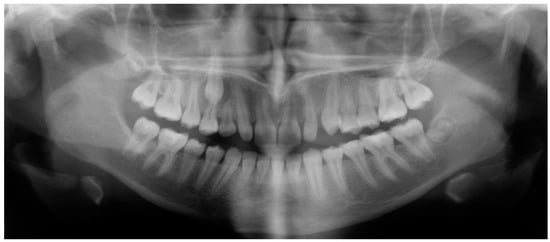

- Evaluation of impacted teeth, a common indication of CBCT in orthodontics. The advantages of CBCT include assessment of the tooth location and position, the stage of development, and status of adjacent teeth. CBCT is justified in these cases, because CBCT has the capability of evaluating the impacted teeth and adjacent structures more accurately than 2D conventional imaging. The benefit–risk ratio is favorable, especially if the CBCT volume is collimated to the impacted tooth. Figure 1, Figure 2, Figure 3 and Figure 4 show an example of impacted maxillary canines, and their proximity to the maxillary lateral incisors. Figure 1 shows an intraoral photograph. The benefit of CBCT acquisition in this case includes the ability to visualize the canines and the lateral incisors in three dimensions, which can be visualized in Figure 2 and Figure 3. In this case, the maxillary right lateral incisor exhibited external root resorption, a finding that would be difficult to see on a conventional 2D panoramic radiograph. Figure 4 shows a Maximum Intensity Projection of a panoramic view derived from the CBCT volume. This unique view is free of magnification, distortion, ghost images, and overlaps frequently seen in conventional 2D panoramic radiography.